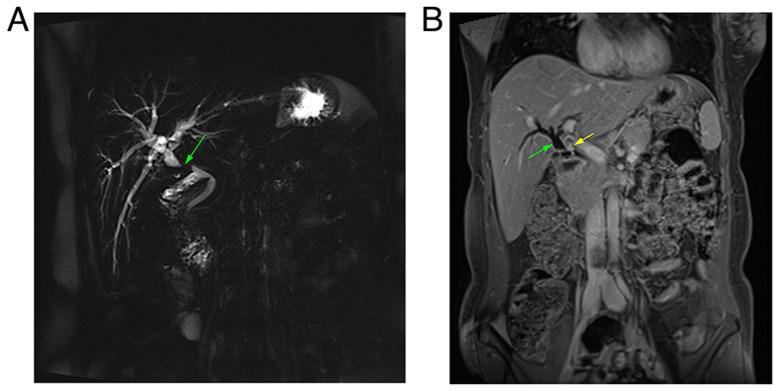

Laparoscopic cholecystectomy has been found to be associated with the development of traumatic neuromas on rare occasions. The present study reports a rare case of post-cholecystectomy biliary tree traumatic neuroma. Herein, a 47-year-old female with a history of laparoscopic cholecystectomy presented with upper abdominal pain and anorexia. Upon an examination, a yellow discoloration of the sclera was observed. Magnetic resonance cholangiopancreatography revealed a dilated proximal bile duct and mild dilatation of the intrahepatic biliary tree due to a stricture. Intraoperatively, a hard bile duct mass was observed with multiple enlarged lymph nodes in the peri-hepatic region. The patient was initially suspected to have bile duct cancer; however, a histopathological analysis of the resected mass revealed a bile duct traumatic neuroma. Biliary traumatic neuromas may be underestimated since they often remain asymptomatic. It is unfortunate that, as traumatic neuromas often lack distinguishing characteristics, no particular radiological findings for traumatic neuromas of the bile duct have been described to date, at least to the best of our knowledge. The rarity of this condition, combined with the absence of a standardized diagnostic modality, renders its diagnosis difficult and can even lead to misdiagnosis as biliary cancer.

腹腔镜胆囊切除术偶尔被发现与创伤性神经瘤的发生有关。本研究报告了一例罕见的胆囊切除术后胆管创伤性神经瘤病例。在此,一名有腹腔镜胆囊切除术病史的47岁女性出现上腹部疼痛和厌食。检查时,发现巩膜黄染。磁共振胰胆管造影显示近端胆管扩张,肝内胆管树因狭窄而轻度扩张。术中观察到胆管有一硬性肿物,肝周区域有多个肿大淋巴结。患者最初被怀疑患有胆管癌;然而,对切除肿物的组织病理学分析显示为胆管创伤性神经瘤。胆管创伤性神经瘤可能未得到充分重视,因为它们通常无症状。遗憾的是,由于创伤性神经瘤往往缺乏特征性表现,至少据我们所知,目前尚未描述胆管创伤性神经瘤的特定影像学表现。这种情况的罕见性,加上缺乏标准化的诊断方法,使得其诊断困难,甚至可能导致误诊为胆管癌。